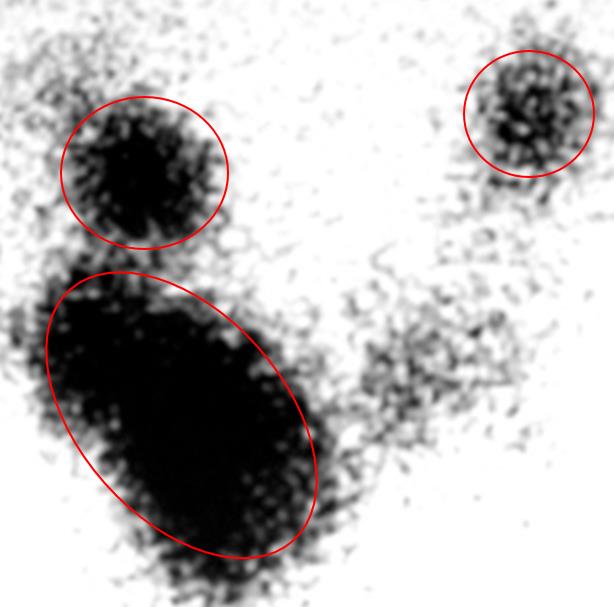

Radioactive iodine uptake (RAIU) results are shown in Figure A. Which of the following is the most likely diagnosis?

Figure/Illustration A is a radioactive iodine uptake (RAIU) test of the thyroid gland showing several areas of focal uptake (red circles). This finding is consistent with a toxic multinodular goiter.

Answer 5: Toxic thyroid adenoma would present very similarly to toxic multinodular goiter; however, the RAIU test will demonstrate a single focal area of increased uptake.